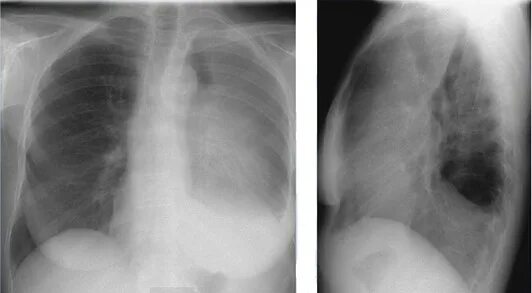

Единичные солидные узелки в легких